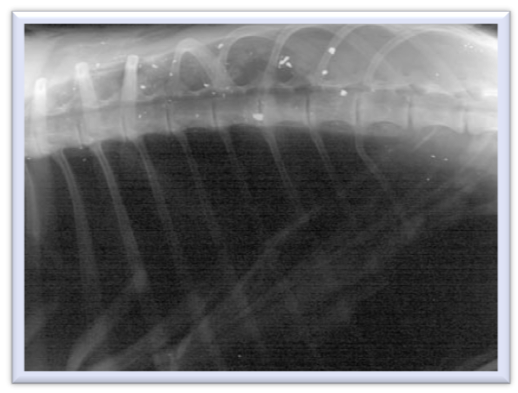

Volunteers quickly began supportive care and chelation therapy (described below) and scheduled radiographs. The x-ray images did not show evidence of the bright metallic opacity that would indicate lead, either from a bullet wound or ingestion of prey containing lead. Doctors suspected the bird had ingested prey containing lead and had already passed the prey through its digestive system, but the lead had been absorbed and was exerting the physiologic effects. Over the course of several days, the bird’s mentation and posture dramatically improved. It began standing upright, fighting handlers, and swallowing food on its own. Subsequent blood lead levels began decreasing. Sadly, the patient succumbed to other injuries sustained while it was debilitated from the lead’s effects. This toxicosis resulted in the bird stranded on the ground before being brought to the clinic.

Within days, a second eagle presented to the wildlife clinic. Similarly, the patient exhibited neurologic signs without evidence of trauma and the team ran a blood sample through the lead analyzer. This time, the level was read as 14.7ug/dL – while still an elevated level, it indicated a better prognosis for the bird. As with the first bird, this eagle did not have radiographic evidence lead in its system. Unfortunately, the eagle died within 24 hours of intake. A necropsy (autopsy) performed revealed evidence of both a viral disease process and head trauma.

A third eagle, presenting within two weeks of the first eagle, exhibited comparable clinical signs. Again, its blood lead levels were too high for the analyzer to read, and at the time that the radiographs were taken there was no evidence of lead. Despite chelation therapy, this eagle was found deceased in its cage before further lead readings could be evaluated.

Diagnosis of lead toxicosis is usually done through bloodwork and radiology. Because our clinic has an in-house lead analyzer, teams are able to determine lead levels quickly – although the decision to do so is based on suspicion. In the above cases, teams did not have access to the radiology department during off-hours, so began treatment prophylactically and took radiographs at the next available time. As is common with lead ingestion, none of the patients had evidence of metallic sources in their bodies.